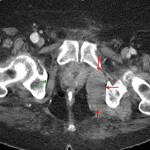

- Asymmetric enlargement and increased density of the left obturator internus muscle with adjacent fat stranding

- Obturator internus intramuscular hematoma

Left obturator internus intramuscular hematoma with a small amount of adjacent retroperitoneal hemorrhage. No evidence of adjacent bony trauma.